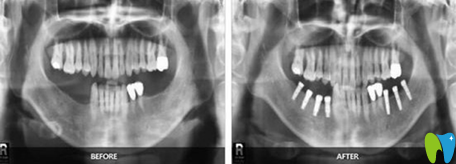

牙齒種植】:

顧客評價:爸爸在這里做的即刻種植,技術挺不錯的,種植完牙齒當天就能吃飯,剛開始我還擔心老年人不好恢復,沒想到恢復也挺不錯的,而且老爸現(xiàn)在胃口挺好的,胃口好了心情也不錯,挺適合老年人的。

福州貝臣齒科種植牙案例